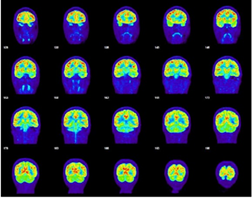

PET scan – assesses metabolic function in the brain.

SPECT scan – assesses blood perfusion (or blood flow/spreading) in the brain.

We use our expertise to review symptoms that are often associated with brain injury, and we follow our clients as they “heal” to determine if the client, family members, or friends observe any changes in cognitive, physical, emotional, behavioral or sleep functioning. We use checklists to cover such items as reduced attention and concentration, memory problems, problems making decisions, depression, impaired judgment, dizziness/balance problems, blurred vision, ringing in ears (also known as tinnitus), alteration of the sense of taste, and/or smell, and many other indications. Often, these forms of deficits are only documented and recognized as a result of a specialized evaluation done by a neuropsychologist, an audiologist, a sleep specialist, or an otolaryngologist (ENT). In other cases, documentation of subtle forms of brain damage may be identified with specialized imaging techniques known as PET scans, SPECT scans, functional MRI evaluations (fMRI), or the latest technology available (including the use of a high-field MRI magnet, known as a 3.0 Tesla, together with Diffusion Tensor Imaging and volumetric assessment).

Microscopic gray and white matter injuries to the brain that occur often in the context of mild, complicated mild, and moderate traumatic brain injury will not be discernible on most diagnostic tests that are performed in an emergency department setting. For example, the gold standard for screening for acquired brain injury in an emergency room setting is the CT Scan. However, with the exception of the reliability of the CT Scan for documenting hemorrhage and/or skull fractures, the CT scan does not reveal much useful information about more subtle damage to brain structures. Likewise, the use of standard clinical MRI found in most community hospitals has limited utility in identifying subtle structural damage. Other tests may be relied upon to corroborate suspected brain injury, including: